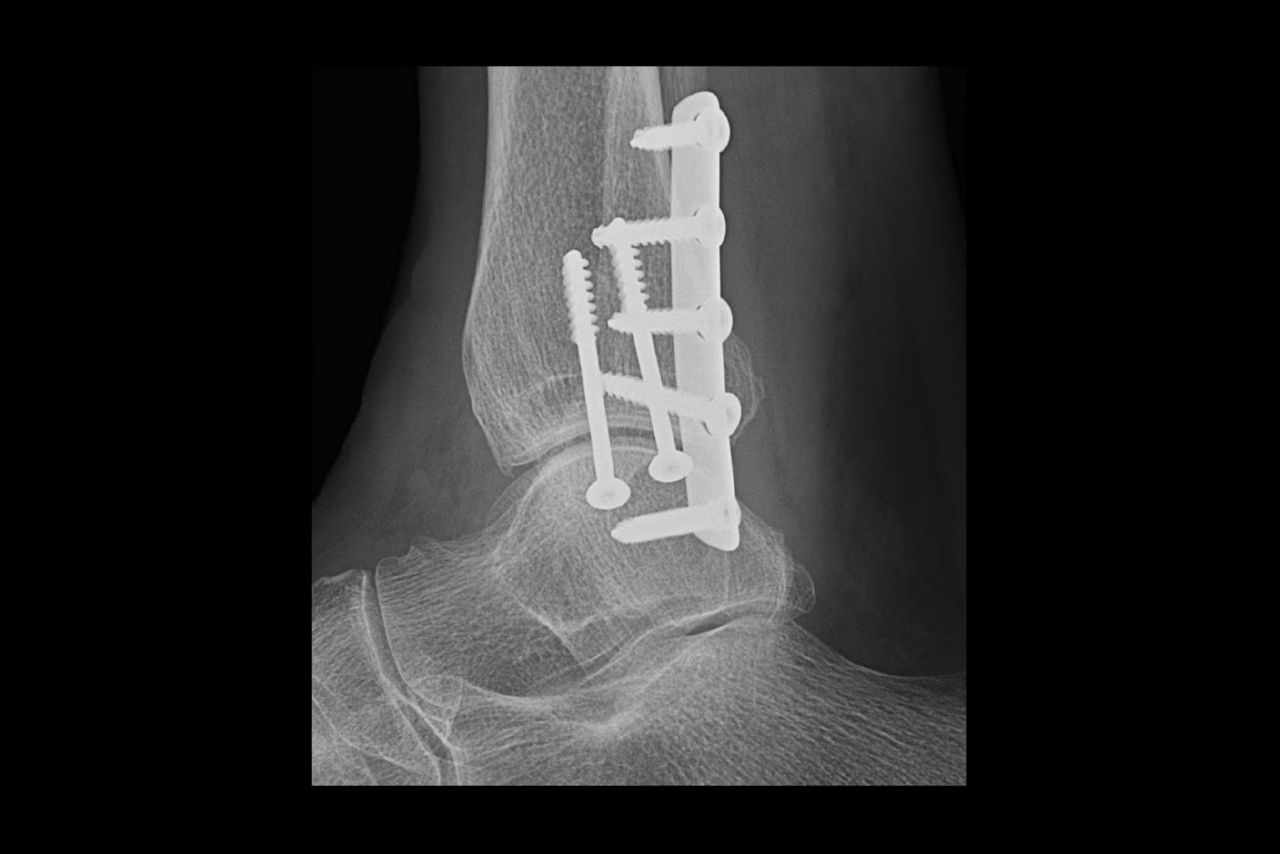

Metal implant handling

See clear bone-metal interface without halo artifact

Helix™ Advanced Image Processing offers unparalleled sharpness, balanced contrast, and optimal brightness, even in the face of dose and patient anatomy variations, as well as challenging metal implants. Available on all of our fixed and mobile X-ray systems, Helix provides consistent performance regardless of exposure technique or exam conditions.